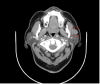

Hemangiomas are benign vascular tumors and are classified into cavernous, capillary, and mixed, with the head and neck area as the most common site. Hemangiomas are common in pediatrics and rare in adults. Diagnosing cavernous hemangioma is challenging and requires a complete history, proper physical examination, and several radiological modalities to improve diagnostic accuracy because it is uncommon in adults. Herein, we present a case of a 66-year-old female Saudi patient with cavernous hemangioma from the diagnosis until the surgical treatment. No previous studies are reported in Saudi Arabia and this is a rare presentation of cavernous hemangioma at this age. Cavernous hemangioma in the parotid gland in adults is uncommon and is difficult to diagnose. Therefore, a thorough physical examination and several radiological modalities are required to improve diagnostic accuracy. The most effective treatment of cavernous hemangioma in adults is surgical resection.